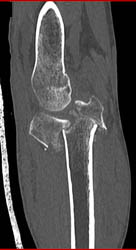

Stent in Axillary Artery Following Injury